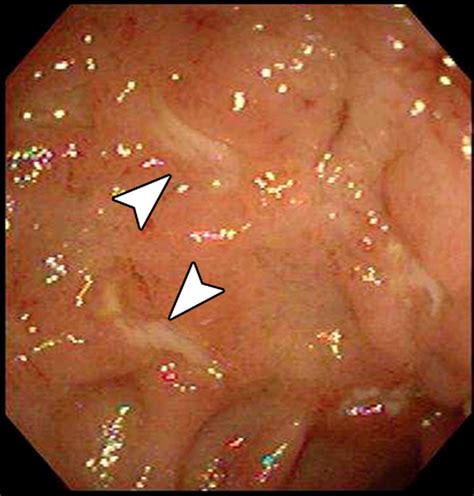

• Crohn's Disease: This is the most common reason for the test, as it allows doctors to look for narrowing (strictures) or inflammation of the bowel wall.

While the Small Bowel Follow Through is a robust tool, it is not without limitations. Its accuracy depends heavily on the patient's bowel motility. In some individuals, the contrast may take an exceptionally long time to move, which can delay results. Furthermore, while it is excellent at identifying structural abnormalities, it cannot provide a biopsy. If the test shows an area of concern, your doctor may follow up with a colonoscopy or a specialized endoscopy to obtain tissue samples for definitive diagnosis.